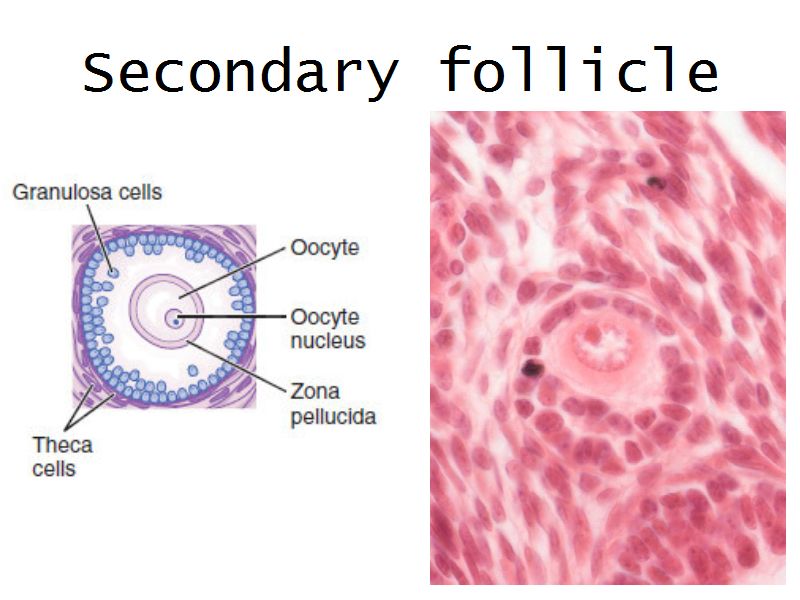

Follicular maturation

- Primordial follicle

- Growing follicle

- Primary follicle

- Secondary follicle

- Mature follicle (Graafian)

Components of a follicle

- Theca

- externa

- interna

- basal lamina

- Granulosa cells

- Antrum

- Cumulus oophorus >> Corona radiata

- Oocyte